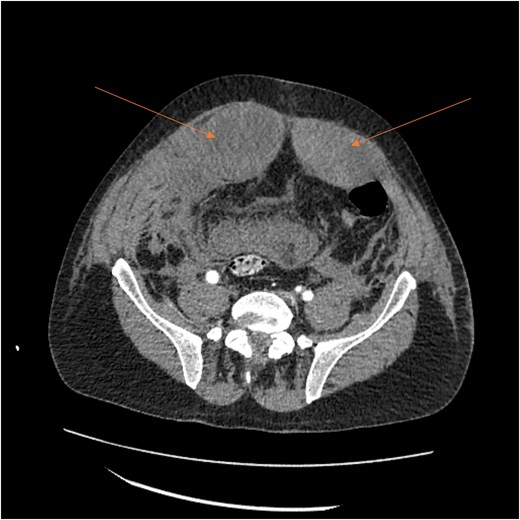

A follow-up CT scan performed 2 days after placement of IVC filter and stopping anticoagulation showed further enlargement of the hematoma (17.5 × 14 × 25.7 cm) and ongoing bleeding. Interventional radiology performed bilateral inferior epigastric artery angiograms, which revealed no ongoing artery bleeding but truncation of the right inferior epigastric artery. Empiric Gelfoam embolization was performed on the left inferior epigastric artery (Fig. 4).

Angiogram of the left inferior epigastric artery (arrow) demonstrating no active bleeding.